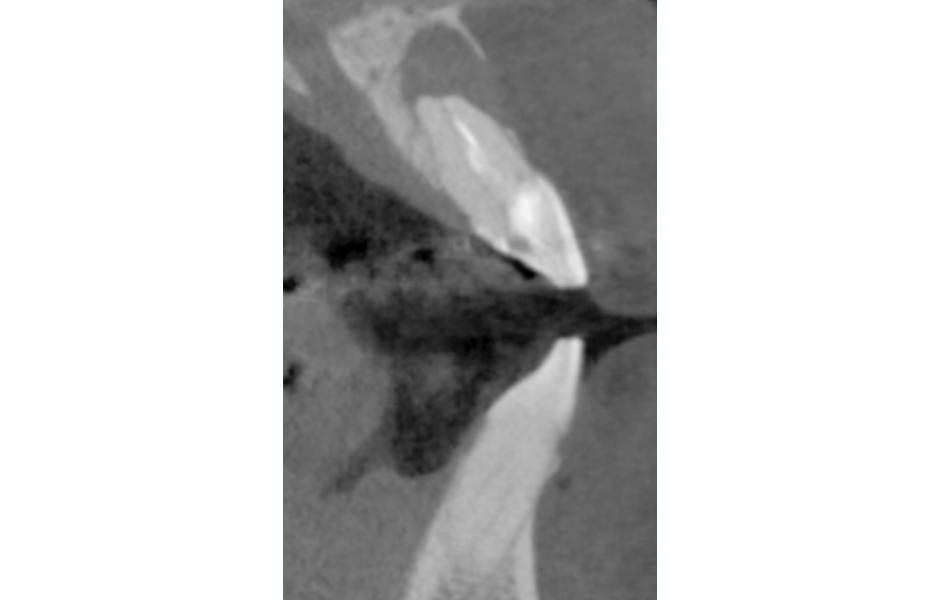

U delegovaného pacienta k reendodoncii udával ošetřující lékař neodstranitelnou kořenovou výplň. Před vlastním reendodontickým ošetřením jsem zhotovil CBCT (obr. 19, 20), abych vyloučil frakturu zubů a zhodnotil průběh kořenového kanálku. Pokud bychom zjistili vertikální frakturu nebo by průběh kořenového kanálku byl nepříznivý, nemělo by smysl se do výkonu pouštět.

U dalšího pacienta jsme zjistili zcestnou preparaci kořenového kanálku (obr. 21, 22).